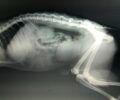

GiannouliLarisasDilitiriasmenos 1

Στις φωτογραφίες βλέπετε τα πρόσφατα θύματα. Το σωματείο στην ανακοίνωση του τονίζει: «Δυστυχώς ο όποιος ψυχασθενής βάζει φόλες στη Γιάννουλη τον τελευταίο καιρό, συνεχίζει ακάθεκτος. Προσοχή οι άνθρωποι που βγάζετε βόλτα έξω τα ζωάκια σας. Εάν δείτε κάποια ύποπτη κίνηση, καταγγείλετέ την άμεσα στην αστυνομία. Εάν δείτε περίεργο φαγητό, μαζέψτε το με ένα γάντι σε μια σακούλα, κ δώστε το στην αστυνομία για ανάλυση. Μην το πετάξετε στα σκουπίδια, καθώς υπάρχουν πολλά ζώα τα οποία τρώνε από εκεί. Όσοι γνωρίζετε τον ή τους δράστες, είστε εξίσου ένοχοι. Η σιωπή είναι συνενοχή!».